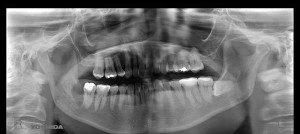

下のパノラマレントゲンは,親知らずが横になった状態で埋まっている(下顎水平埋伏智歯)状態でした。

さらに,親知らずの根の先と下顎管が近接しているため,CT撮影を必要とするケースでした。

赤い丸が親知らずで,黄色い線が下顎管になります。